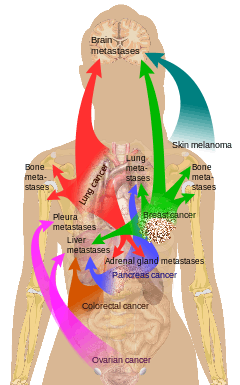

Bone is the third most common location for metastasis, after the lung and liver.[5] While any type of cancer is capable of forming metastatic tumors within bone, the microenvironment of the marrow tends to favor particular types of cancer, including prostate, breast, and lung cancers.[3] Particularly in prostate cancer, bone metastases tend to be the only site of metastasis.[2] The most common sites of bone metastases are the spine, pelvis, ribs, skull, and proximal femur.[6]